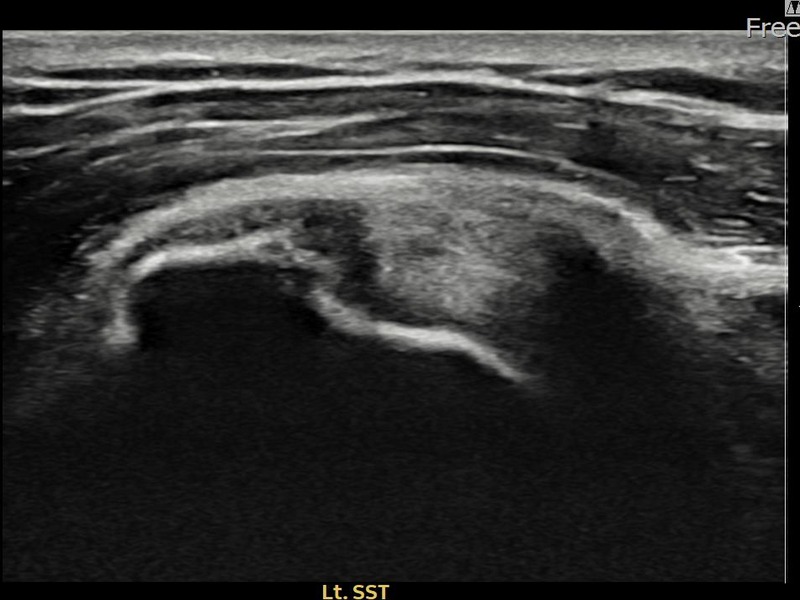

김ㅇㅇ님 · 좌측 극상근건 점액낭면측 부분파열

좌측 어깨 광범위 파열로 팔 들어올리기가 매우 어려웠습니다. 축소봉합술 시행 후 점액낭면측 힘줄 구조가 안정화되었습니다.